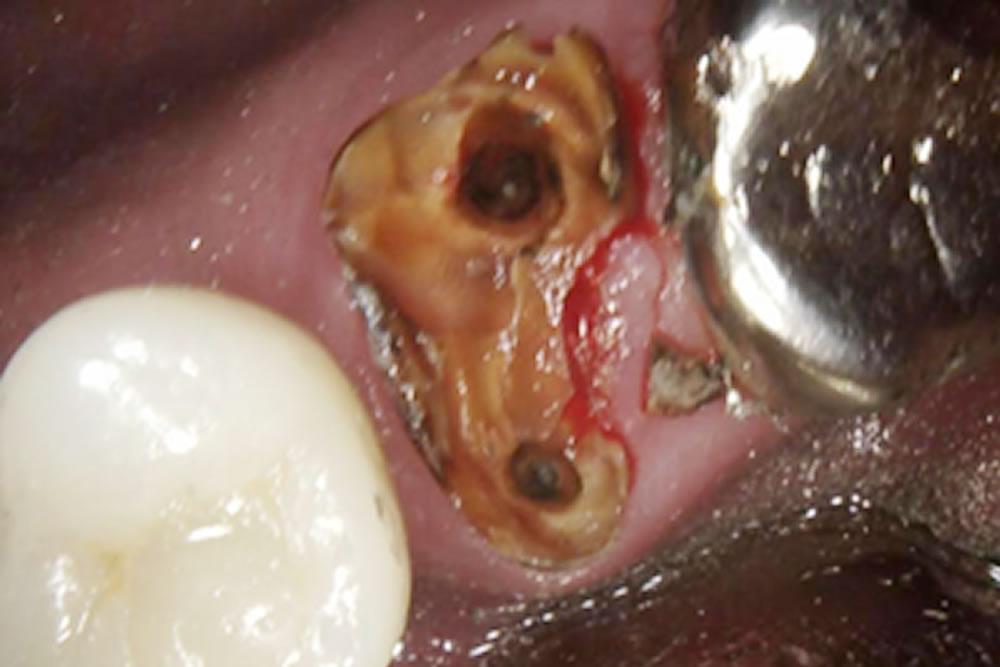

上部の銀歯を除去したところ、中の歯が虫歯と破折により保存する事ができなくなっていました。

手前にインプラントが入っているため、できるだけ歯茎が下がらないように治療をする事と、CT写真にて上顎洞までの骨の厚みが無い事がわかったので、まずは歯を抜いて骨が落ち着くまで4ヵ月待ちインプラントオペを行う事にしました。

今回は上顎洞までの骨の厚みが足りなかった為に上顎洞粘膜を挙上し、骨を作ると同時にインプラント体を埋入していきました。粘膜を挙上する方法としては水の圧力を利用して行っていきました。